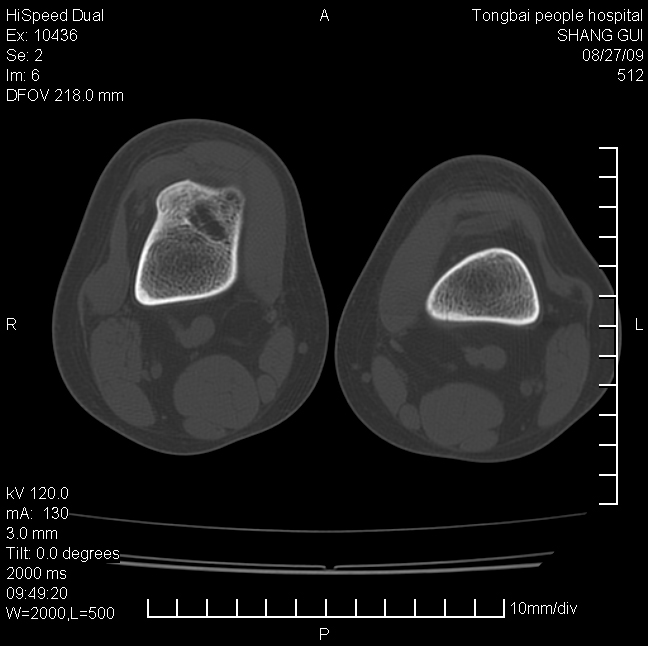

女,12岁。无意发现股骨下端隆起。局部皮肤颜色,温度无异常。

考虑右股骨下端骨纤维结构不良;不排除非骨化性纤维瘤。

不能排除,其实平片更直观。宽基底骨软骨瘤皮质与骨干皮质相连,髓腔与髓腔相通,骨纹理走行方向一致,部分软骨帽可有钙化,本例病变内“磨玻璃状、多囊状改变”比较符合骨纤。